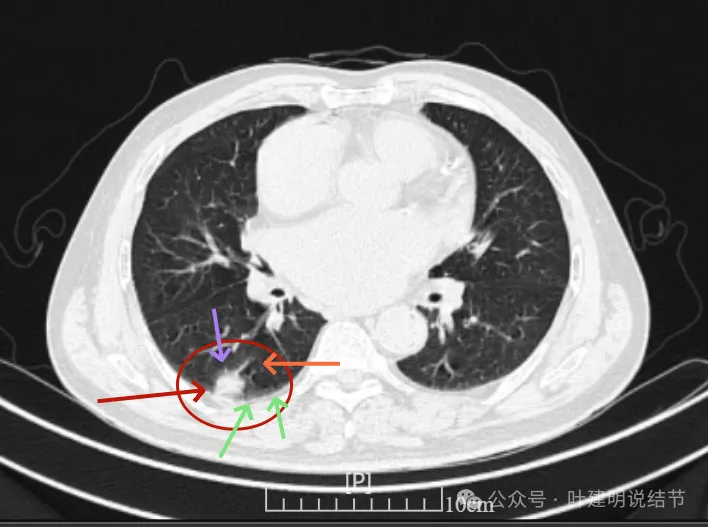

这是冠状位、矢状位与轴位的影像。

增强纵隔窗见病灶内部的密度好像低于周围区域,像坏死。

邻近胸膜无牵拉,灶内有低密度区,局部有点状液性密度。邻近胸膜较为广泛的增厚或胸膜反应。

病灶与胸膜接触面宽,病灶内部密度较低。